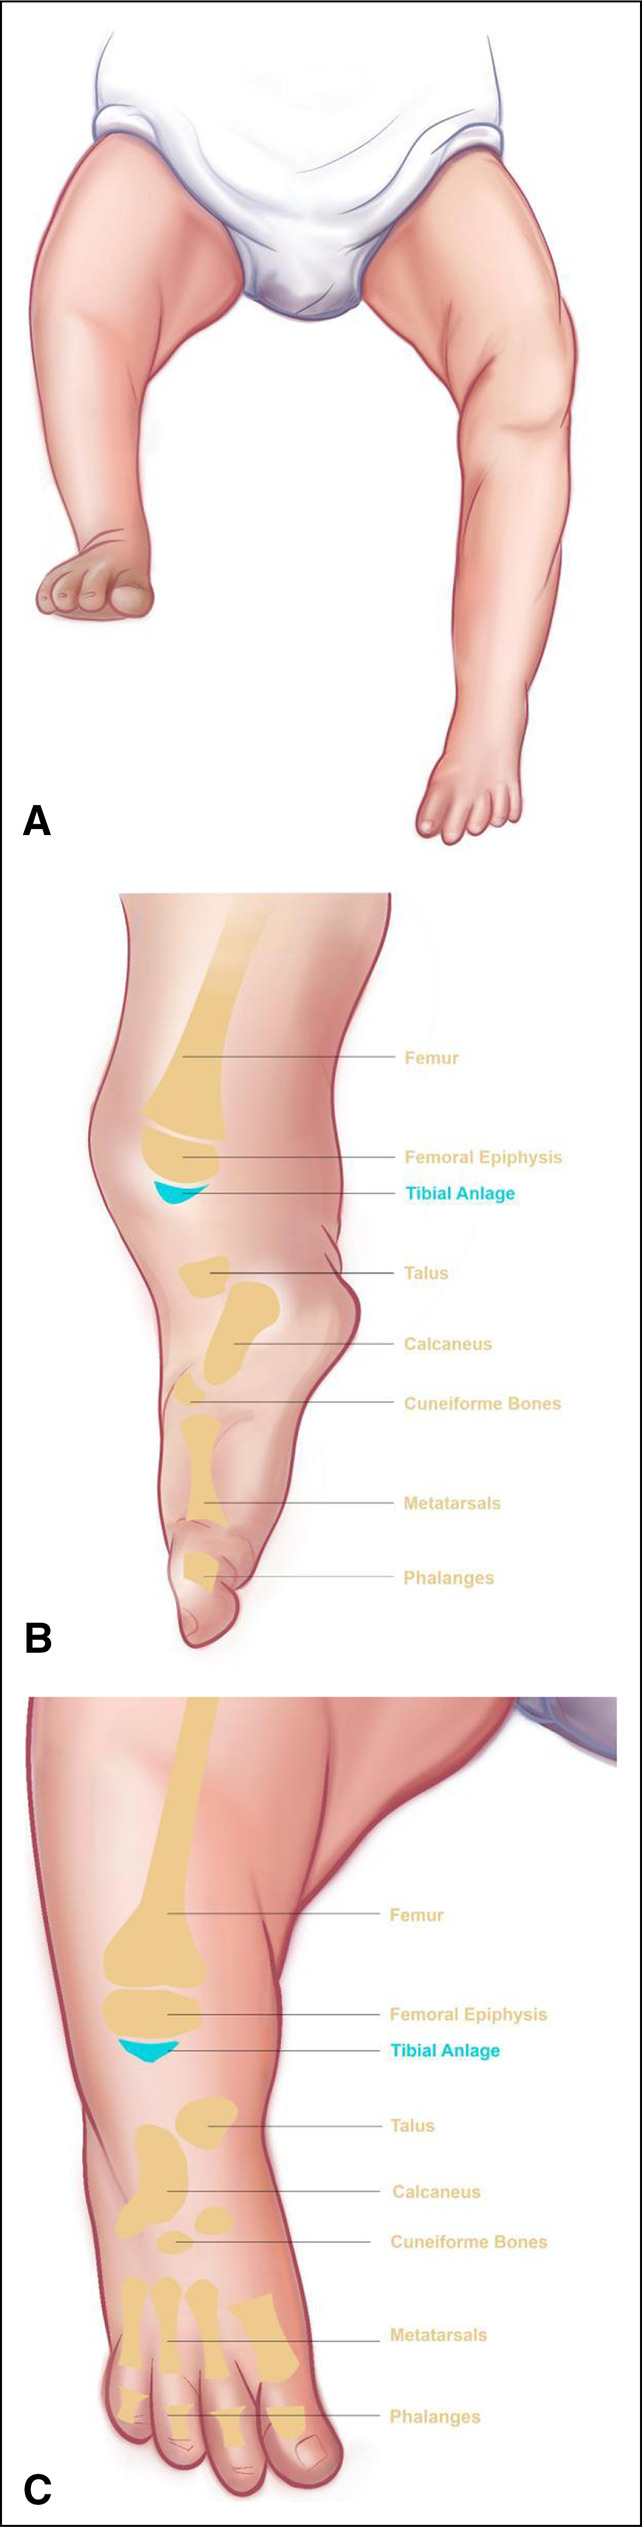

胫骨偏瘫是一种罕见的先天性缺陷,具有挑战性的治疗。适当的护理因许多亚型和相关的膝关节和踝关节畸形而异。截肢仍然是最被接受的治疗方法,但通常不被家庭所接受。因此,也提供了其他重建方案。在以下两个病例中,我们通过踝关节融合而不是截肢进行了膝关节重建。这项技术在以前的文献中没有报道过,被命名为Cabukoglu重建技术或cruris成形术。

Tibial hemimelia is a rare congenital deficiency that is challenging to treat. Appropriate care varies due to the many subtypes and associated knee and ankle deformities. Amputation is still the most accepted treatment, but it is not generally preferred by families. Consequently, other reconstruction options have been made available as well. In the following two cases, we performed knee joint reconstruction by fusion of the ankle joint instead of amputation. This technique has not been reported before in the literature and has been named as Cabukoglu reconstruction technique or cruris plasty.